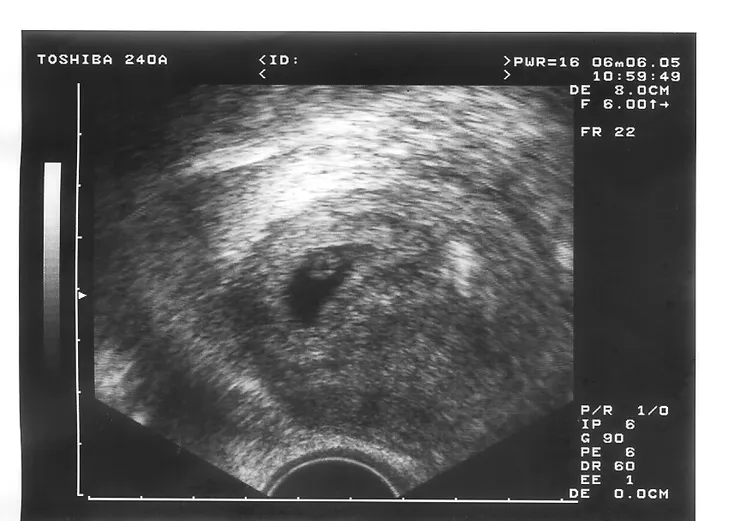

那天進診間後,醫生聽了我的來意,他說:「胚胎還小,所以要照陰道超音波喔!」

照的時候,醫生把簾子移開,指著螢幕對我說:「妳看!現在正在跳的這個就是胚胎,有心跳,是六週的正常大小。」

看到螢幕上在跳動的胚胎,那一剎那,我好想哭!這種感覺實在很難以形容,我實在很難想像,竟然會有一個生命正在我的身體內孕育,真是一種很奇妙的感覺。

我跟醫生說:「可不可以把這個印下來給我?」

「本來就會印給妳。滿12週後再來拿媽媽手冊。」

於是我就拿著寶貝的這張超音波照感動地離開醫院。